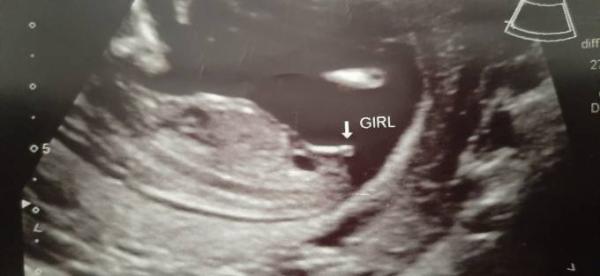

Hallo Visa! Also mir wurde das von einem Arzt, der nur Ultraschalle den ganzen Tag macht und darauf spezialisiert ist, so erklärt: Beim Jungen ist der Schnippi vertial (jetzt von der Seite gesehen) und beim Mädel horizontal. Der vom Mädchen bildet sich dann zur Klitoris zurück. Ich hänge dir mal ein Bild meiner letzten SS dran und es blieb beim Mädchen. Das Bild wurde bei 12+5 damals gemacht. Liebe Grüße

Bild zu

Oh danke. Ich bin mir nun garnicht mehr sicher. Ich zeig dir auch mal ein Bild. Was meinst du?

Mit meinem Leihen - Wissen würde ich auch auf einen Junge tippen Wir haben Montag den ersten großen Ultraschall, da erfahren wir auch das Geschlecht Nach meiner kleinen Untersuchung am Mittwoch, tippe ich bei uns auch auf einen Jungen, bin seeeehr gespannt!